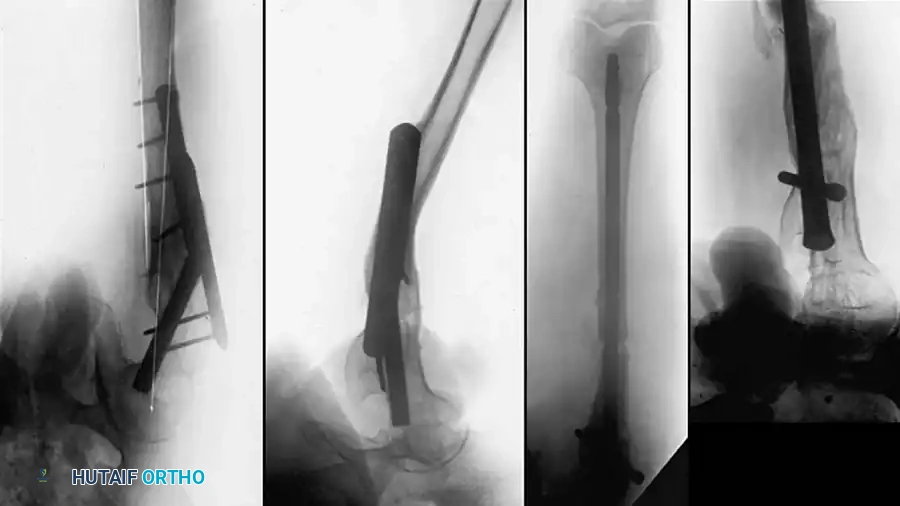

Fig. 55-18 A, Rotational malunion of femur after unlocked intramedullary nailing. B, Correction of malunion with proximal femoral derotational osteotomy and locked nailing. C, Healed osteotomy.

Technique:

1. Place the patient supine or lateral on a fracture table.

2. Expose the malunion site. The bone is divided through the plane of the malunion using a reciprocating saw. Alternatively, to minimize thermal necrosis, the plane can be outlined with multiple drill holes and completed with a sharp osteotome.

3. Ream the medullary canal sequentially.

4. Insert the interlocking nail, ensuring rotational correction is held perfectly before deploying the distal locking screws.

5. Autogenous iliac crest bone grafting is highly recommended to stimulate osteogenesis at the osteotomy site.

Clinical example demonstrating restoration of the mechanical axis using a statically locked intramedullary nail following diaphyseal osteotomy.

Fig. 55-19 A, Distal femoral fracture with 30-degree varus malunion. B, External fixation was used to correct deformity before plating. C, After osteotomy and plating.

Müller, Strosche, and Scheuer reported high union rates using plate osteosynthesis combined with autogenous bone grafting for angular and rotational deformities. Chiodo et al. successfully utilized oblique osteotomies combined with closing wedges to correct multi-planar deformities (coronal, transverse, and sagittal), stabilizing them with 4.5-mm plates.

Fig. 55-20 A and B, Malunion of subtrochanteric fracture with severe internal rotational deformity. C and D, Corrective osteotomy, implant removal, and fixation with proximal interlocking Grosse-Kempf medullary nail.

These require robust fixation using a cephalo-medullary interlocking nail (reconstruction nail), a 95-degree blade plate, or a dynamic condylar screw system inverted for proximal use.